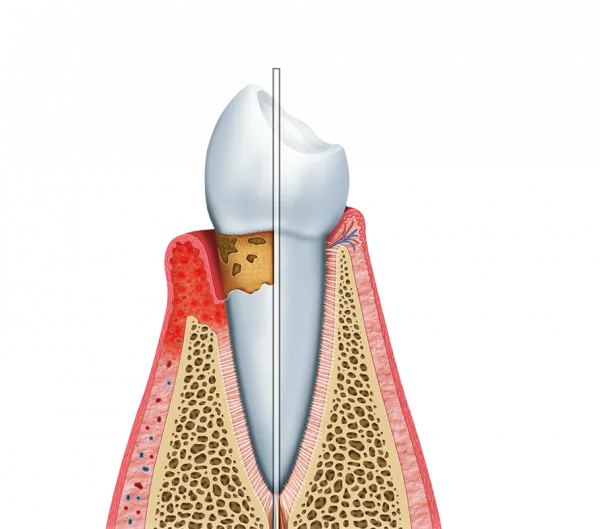

A Periodontia é vital para prevenir doenças silenciosas que, se não tratadas, podem levar à perda dentária e comprometer a estrutura óssea da face no cotidiano.

O dentista periodontista é o profissional capacitado para identificar e tratar doenças gengivais em diferentes estágios, como a gengivite e a periodontite. A intervenção técnica oferece vantagens nítidas para o paciente:

Identificação Precoce: Detecção de inflamações antes que atinjam o osso alveolar;

Controle de Infecções: Tratamento eficaz de sangramentos e focos bacterianos;

Preservação Estrutural: Prevenção da retração gengival e da perda de dentes naturais.

A saúde bucal está diretamente ligada à saúde do corpo, e o controle das bactérias periodontais ajuda a prevenir complicações em outras áreas da saúde.

Sintomas Visíveis: Sangramento nas gengivas ao escovar os dentes ou usar fio dental;

Alterações na Arcada: Retração gengival (dentes parecendo “mais compridos”) ou mobilidade dental;